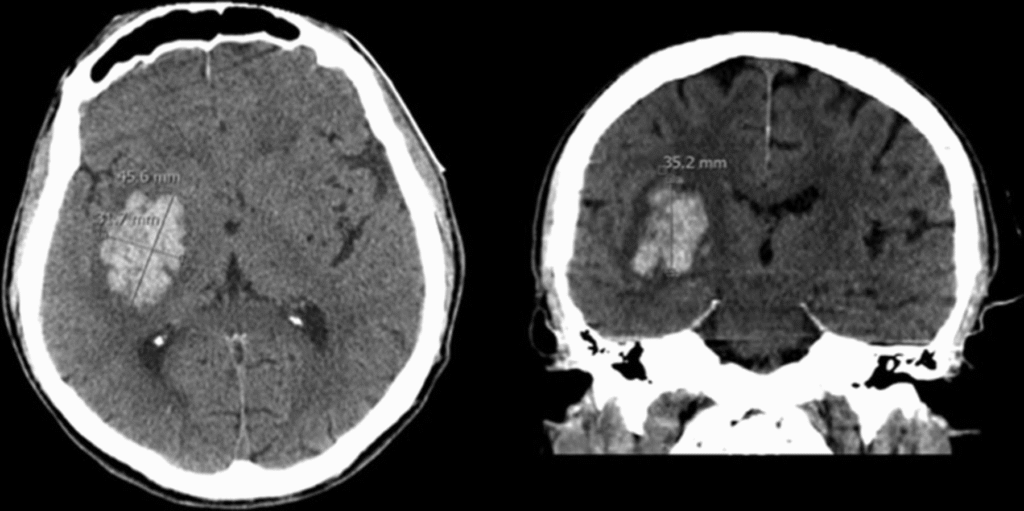

- ICB: Hypertonie, Antikoagulation, CCT: hyperdens intrazerebral → intensivmedizinisch, Gerinnung korrigieren

- CCT nativ (Blutung, Ödem, Fraktur, Mittellinienshift)

- Kausal: Hämatomevakuation, Trepanation